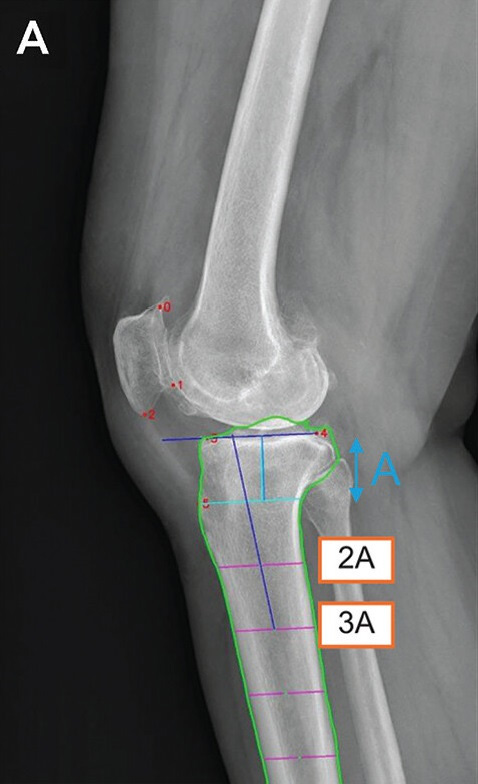

• 딥러닝 모델의 측정 매커니즘. 6개의 해부학적 기준점(빨간 점)을 자동 인식한 후, 경골의 관절선과 중심축(파란 선)을 결정해 경골 후방 기울기를 계산한다. /이미지 제공=서울대병원

▲ 딥러닝 모델의 측정 매커니즘. 6개의 해부학적 기준점(빨간 점)을 자동 인식한 후, 경골의 관절선과 중심축(파란 선)을 결정해 경골 후방 기울기를 계산한다. /이미지 제공=서울대병원

서울대병원 정형외과 노두현 교수·김성은 연구교수 연구팀은 미국 미네소타대, 노르웨이 베르겐대와 공동으로, 2009~2019년 사이 촬영된 무릎 엑스레이 1만여 건을 학습한 딥러닝 모델을 개발했다. 이 모델은 무릎뼈의 6개 해부학적 기준점을 자동 인식해 관절선과 중심축을 계산하고, 이를 통해 경골 후방 경사각을 빠르고 정확하게 산출한다.